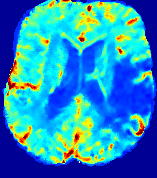

4.3.2 Diffusion Imaging via Advection-Diffusion

Slice #1Slice #2Slice #3Slice #4Slice #5Slice #6Dgtsuperscript𝐷gtD^{\text{gt}}Refer to captionRefer to captionRefer to captionRefer to captionRefer to captionRefer to captionDestsuperscript𝐷estD^{\text{est}}Refer to captionRefer to captionRefer to captionRefer to captionRefer to captionRefer to captionRefer to caption0.300.300.300.240.240.240.180.180.180.120.120.120.060.060.060.000.000.00(mm2/s)𝑚superscript𝑚2𝑠(mm^{2}/s)𝐕est𝟐subscriptnormsuperscript𝐕est2\|\bf{V}^{\text{est}}\|_{2}Refer to captionRefer to captionRefer to captionRefer to captionRefer to captionRefer to captionRefer to caption0.00300.00300.00300.00240.00240.00240.00180.00180.00180.00120.00120.00120.00060.00060.00060.00000.00000.0000(mm/s)𝑚𝑚𝑠(mm/s)

Figure 15: PIANO identifiability testing: diffusion imaging via advection-diffusion. Top row shows Dgtsuperscript𝐷gtD^{\text{gt}} used for simulating ground truth pure diffusion. Rows below show the estimated Destsuperscript𝐷estD^{\text{est}} and 𝐕est2subscriptnormsuperscript𝐕est2\|{\bf{V}}^{\text{est}}\|_{2} on corresponding slices. Note that the plotted value scale for 𝐕est2subscriptnormsuperscript𝐕est2\|{\bf{V}}^{\text{est}}\|_{2} is 0.01 of that for Dgtsuperscript𝐷gtD^{\text{gt}} and Destsuperscript𝐷estD^{\text{est}}.

Similarly, we test the behavior of PIANO when estimating both advection and diffusion from a pure diffusion-driven process. The goal is to determine if PIANO is able to recognize that there is only diffusion governing the given concentration time-series. We use the same ‘Diffusion Imaging’ data simulation of Sec. 4.2.1 as the concentration dataset, PIANO estimates both velocity 𝐕estsuperscript𝐕est{\bf{V}}^{\text{est}} and diffusivity Destsuperscript𝐷estD^{\text{est}}. Estimation results in Fig. 15 confirm PIANO’s identifiability again: the estimated 𝐕est2subscriptnormsuperscript𝐕est2\|{\bf{V}}^{\text{est}}\|_{2} is almost invisible compared to Destsuperscript𝐷estD^{\text{est}}, even plotted with a 1%percent11\% value range compared to that for Destsuperscript𝐷estD^{\text{est}}. On the other hand, Destsuperscript𝐷estD^{\text{est}} achieves comparable estimation performance as ‘Diffusion Imaging via Diffusion’ in which PIANO predicts Destsuperscript𝐷estD^{\text{est}} alone (shown in Fig. 13).